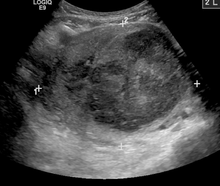

| A very large (9cm) fibroid of the uterus which is causing pelvic congestion syndrome as seen on X-ray computed tomography | |

Women with pelvic congestion syndrome have a larger uterus and a thicker endometrium. 56% of women manifest cystic changes to the ovaries,[4] and many report other symptoms, such as dysmenorrhea, back pain, vaginal discharge, abdominal bloating, mood swings or depression, and fatigue.[2][3]